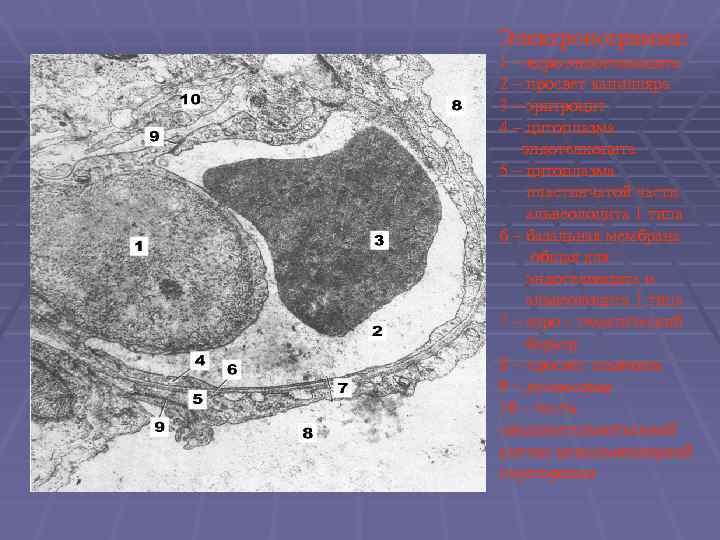

Электронограмма: 1 – ядро эндотелиоцита 2 – просвет капилляра 3 – эритроцит 4 – цитоплазма эндотелиоцита 5 – цитоплазма пластинчатой части альвеолоцита 1 типа 6 – базальная мембрана общая для эндотелиоцита и альвеолоцита 1 типа 7 – аэро – гематический барьер 8 – просвет альвеолы 9 – десмосомы 10 – часть соединительнотканной клетки межальвеолярной перегородки